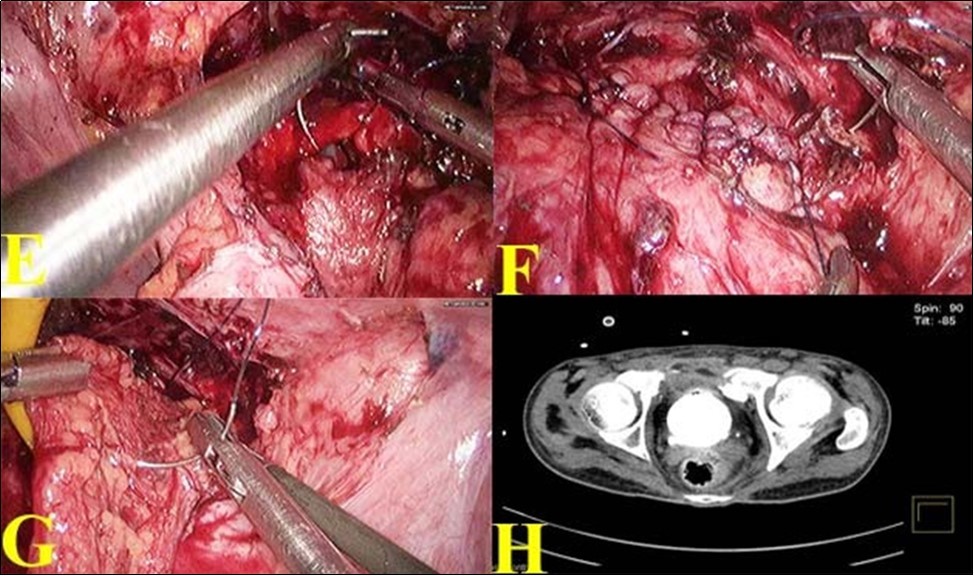

17-year-old male was referred with a urethral and suprapubic catheter and complaints of fever and pyuria for 6 weeks. The prior record showed that he was admitted 2 months earlier following a road traffic accident with pain in the lower abdomen, hematuria and anal tear. He was initially stabilized and was evaluated with a CT scan which showed a pelvic fracture; extra-peritoneal bladder injury at two sites in the antero-lateral wall. The attending trauma surgeon did diverting colostomy for anal tear and supra-pubic cystostomy. Patient was referred after 6 weeks of fever and pyuria. Clinical examination revealed fair general condition and abdomen examination revealed a well-healed midline laparotomy scar along with colostomy, supra-pubic and urethral catheters. Bio-chemical investigation revealed normal renal function. Urine culture was positive and he was treated with culture specific antibiotic as he was symptomatic. After 7 days of treatment, computerized tomographic cystogram was done, which showed bilateral extra peritoneal bladder tears of about 15mm in length with extravasation of contrast from the anterolateral wall of bladder close to bladder neck bilaterally. Figure 1(A). Considering the persistence of gross extravasation of bladder contrast even after 7 weeks; laparoscopic repair of the bladder rent was planned.

Sigmoid colostomy was covered with sterile adhesive. With the patient in supine position, using 4 ports, laparoscopy was done. Figure 1 (B). There were extensive omental and bowel adhesions, which were released. Bladder was dropped and the SPC was removed. Extensive fibrosis was noted between the anterior wall of the bladder and pubic bone. Further mobilization of anterior wall of bladder revealed a bone spicule impinging on the left anterolateral wall and causing a rent of about 15 mm. The other rent was noticed on the right anterolateral wall close to the bladder neck about 15 mm long. Figure 1 (C). The bone spicule was removed.

Diluted methylene blue solution was instilled through urethral catheter to confirm that there were no other rents. The two rents were connected and made into a single large rent. Figure 1 (D). The edges were trimmed and closed using 3-0 absorbable barbed suture and omentum was tacked over the suture line.

Figure 1.A. Pre-operative CT showing contrast extravasation in anterior wall with bony spicule; B. Port Placement for bladder repair; C. Bladder rent identified by methylene blue; D. Two defects joined into a single cystotomy

A. Pre-operative CT showing contrast extravasation in anterior wall with bony spicule; B. Port Placement for bladder repair; C. Bladder rent identified by methylene blue; D. Two defects joined into a single cystotomy